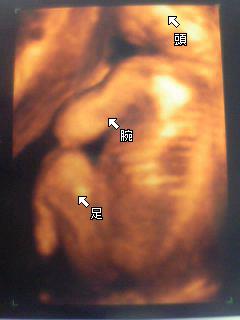

今日は、定期健診。22w(6ヶ月) |